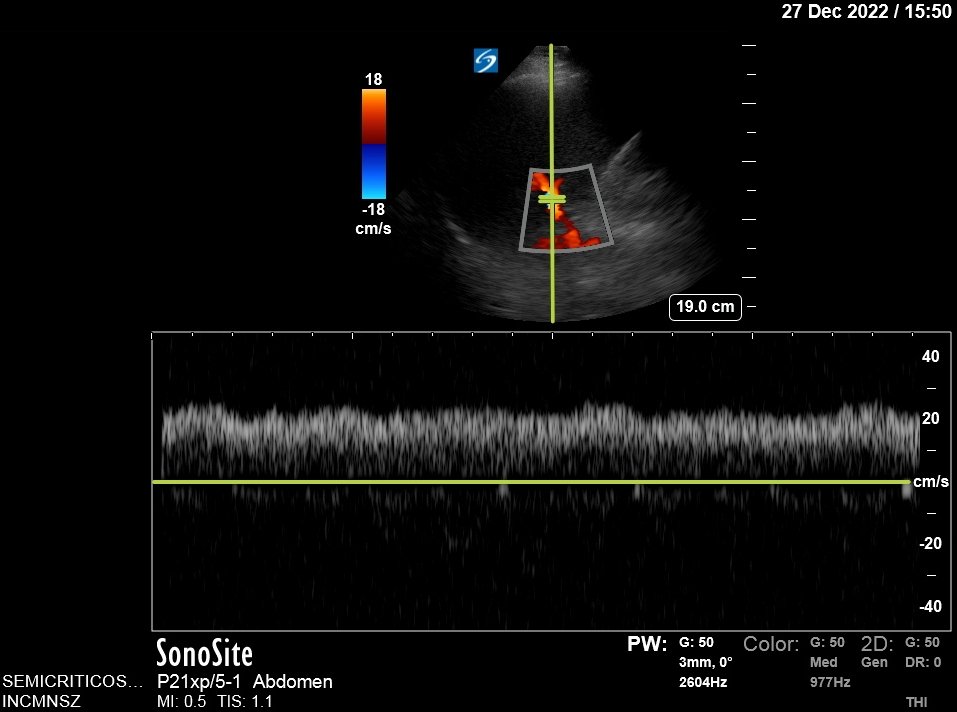

Plethoric IVC, Portal Pulsatility 39%.

Hepatic Vein Doppler shows characteristic D wave reversal!

Again: This is strongly suggestive of Tamponade!!🚨

However, liver congestion got worse: Portal Vein Pulsatility now 62%. This is not good, especially since LFTs came back ⬆️⬆️⬆️

Portal Vein is no longer pulsatile

Hepatic vein shows no D wave reversal